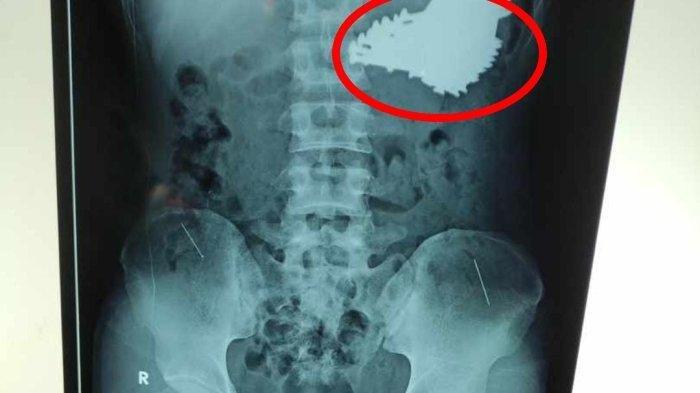

Mengutip TribunJabar.id, paku-paku tersebut diketahui setelah hasil rontgen pasien keluar.

Hasil rontgen tersebut memperlihatkan banyakan paku berukuran besar yang berada di lambung pasien.

Dari situ, dokter lantas memeriksakan pasien ke bagian radiologi dan menjalani rontgen.

Dari hasil foto rontgen, diketahuilah banyak paku berukuran besar yang bersarang di lambung pasien.